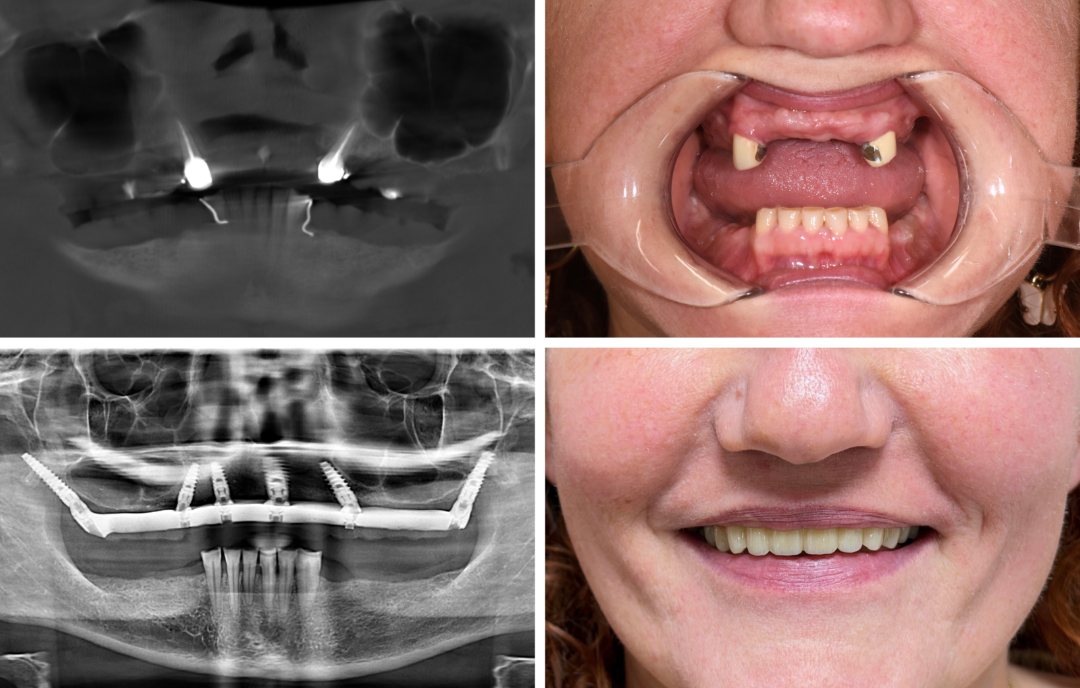

Die Patientin war langjährige Prothesenträgerin. Dies führte zu einem so ausgeprägten Knochenabbau, dass herkömmliche Implantate nur bedingt möglich waren. Zusätzlich war die Patientin zu keinem Zeitpunkt bereit, zahnlos zu sein.

Die Patientin erhielt eine navigierte Full-Arch-Rekonstruktion im Oberkiefer mit Zygoma- und Pterygoidimplantaten. Sechs Monate später wurde auch der Unterkiefer in ITN versorgt. Aktuell trägt die Patientin im Unterkiefer noch ein Provisorium.

Ohne aufwendigen Knochenaufbau erhielt die Patientin festsitzende Zähne im Ober- und Unterkiefer. Während der gesamten Rehabilitationszeit trug sie, wie gewünscht, stets eine provisorische feste Brücke. Demnächst beginnt der Zahnarzt mit der definitiven Versorgung des Unterkiefers. Der Workflow ist dabei vereinfacht, da die Kiefergelenke und der Biss bereits adjustiert sind.